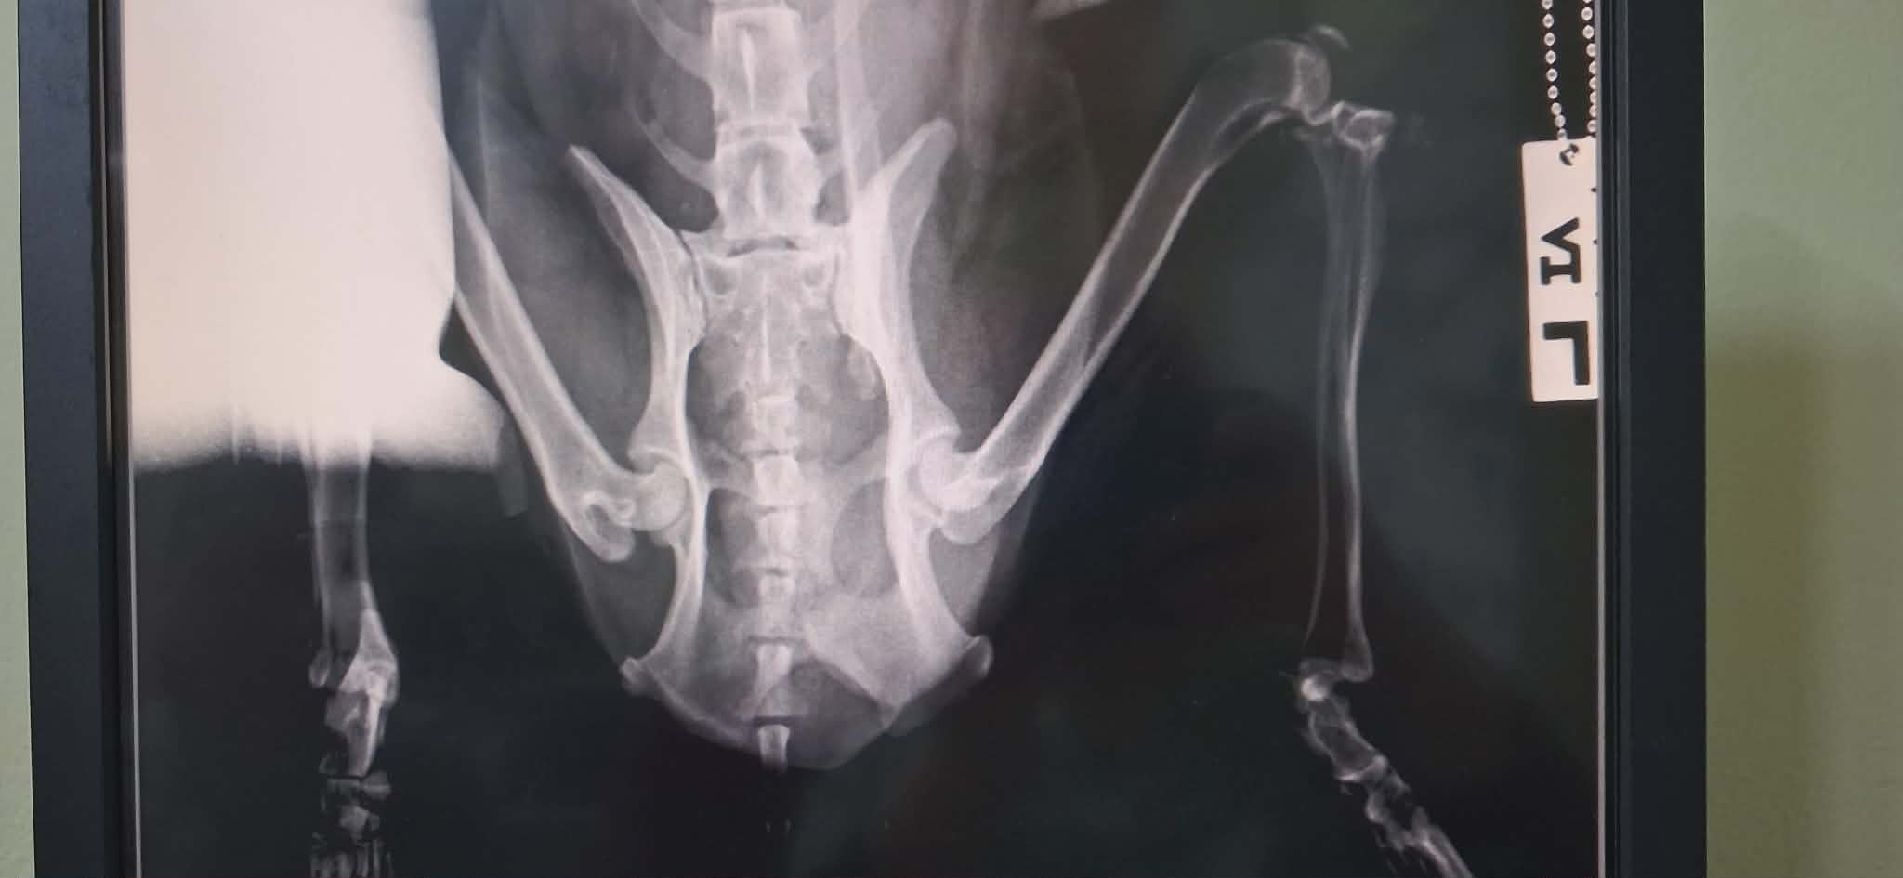

Notfellchen aufgrund von: verheilten Beckenverletzungen nach Autounfall

https://www.tiere-in-not-griechenland.de/unsere-hunde/zuhause-gesucht/notfellchen#sigProId2da8d91ad0